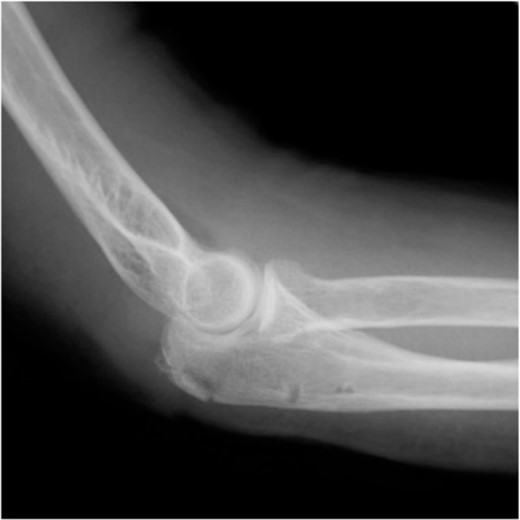

Postoperative radiography revealed reduced bone fragmentation (Fig. 5). The elbow was immobilized at 90° for 1 week postoperatively; range-of-motion exercises were started in postoperative week 2. Radiographs obtained 4 months postoperatively showed bone union (Fig. 6). At 18 months postoperatively, the patient had a range of motion of 140° flexion and 0° extension. The disability of the arm, shoulder and hand score was 0.

Postoperative lateral elbow radiographs. The bone fragment is reduced and fixed.